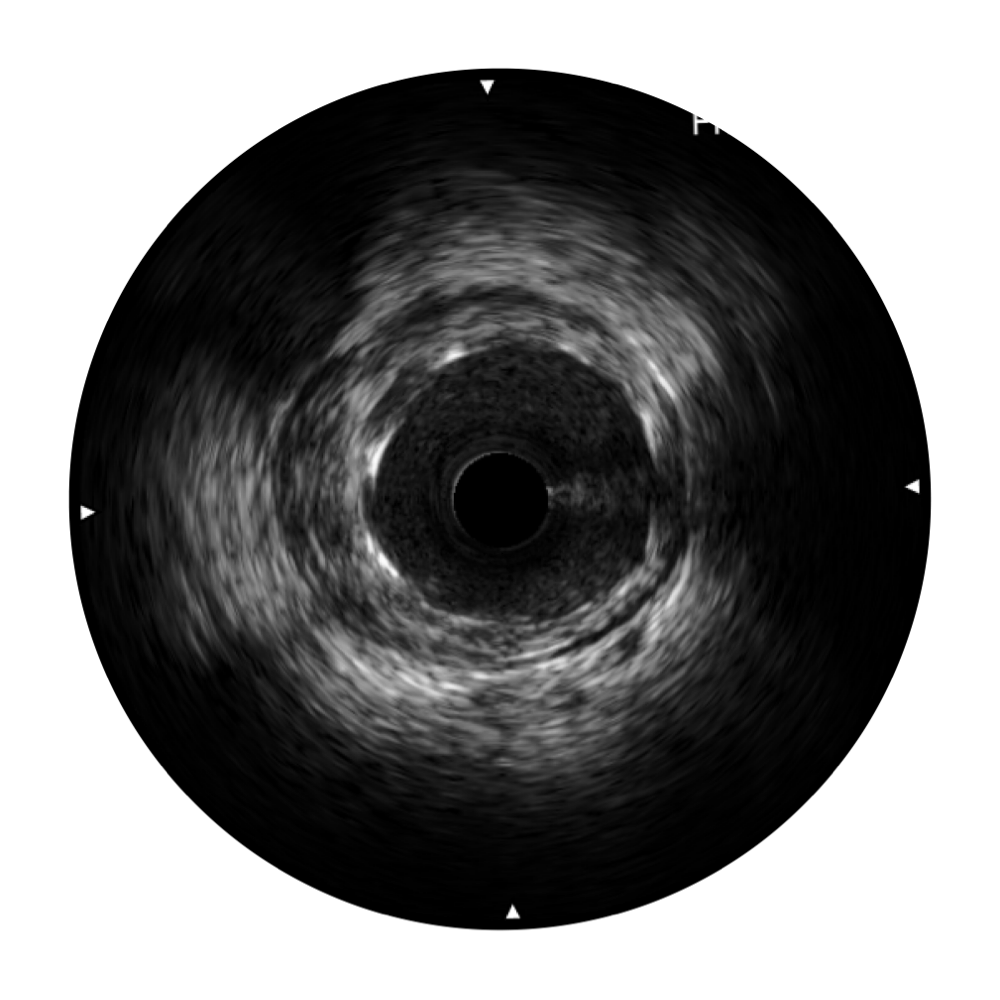

• 不朽情缘宽频IVUS图像

• 传统IVUS图像

对比传统IVUS导管成像,不朽情缘宽频IVUS图像的近场支架梁显影更细腻,远场中膜外血管仍清晰可辨,兼顾远中近,兼顾分辨力与穿透深度